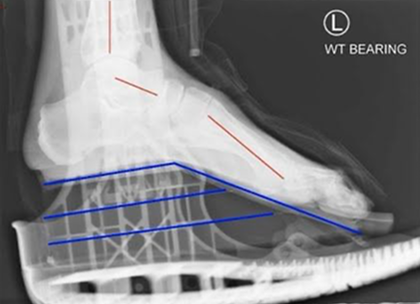

X-ray Comparison: VACOped vs Aircast

Aircast achieves 28° ankle plantarflexion with wedges

VACOped maintains consistent 48° ankle plantarflexion

Key findings:

- VACOped may achieve 48° ankle plantarflexion vs. 28° in Aircast

- Aircast appears to create equinus through midfoot compensation

- VACOped’s positioning may be closer to cast immobilization

- Some studies suggest VACOped shows lower tendon loading during walking